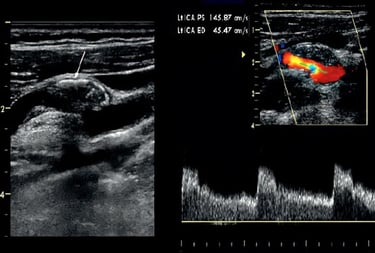

Our Vascular course unfolds as a protocol-driven journey through arterial, venous, and physiologic Doppler mastery.

We begin by aligning participants around the core vascular anatomy and hemodynamic principles that make each Doppler signal meaningful. Early scanning sessions focus on smooth image acquisition and accurate angle alignment across major vascular beds.

As your foundation solidifies, scanning expands to encompass a systematic, total-body protocol — carotid, upper and lower extremities, abdominal vessels, transcranial windows, and venous insufficiency surveys — all with immediate faculty feedback. Doppler interpretation is integrated alongside anatomy, teaching you how to recognize and quantify pathology rather than memorizing isolated signs.